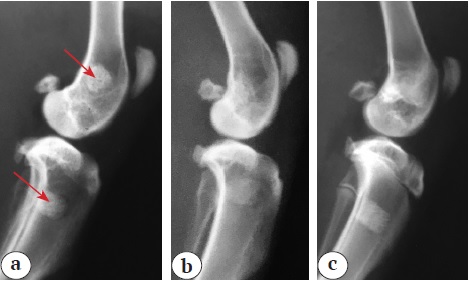

The implantation zones in animals of all groups were well visualized on X-rays on the day of the surgery (Fig. 1).

Fig. 1. X-rays of the implantation area on the day of the surgery: a — Group 1 (arrows indicate the implantation area); b — Group 2; c — Group 3